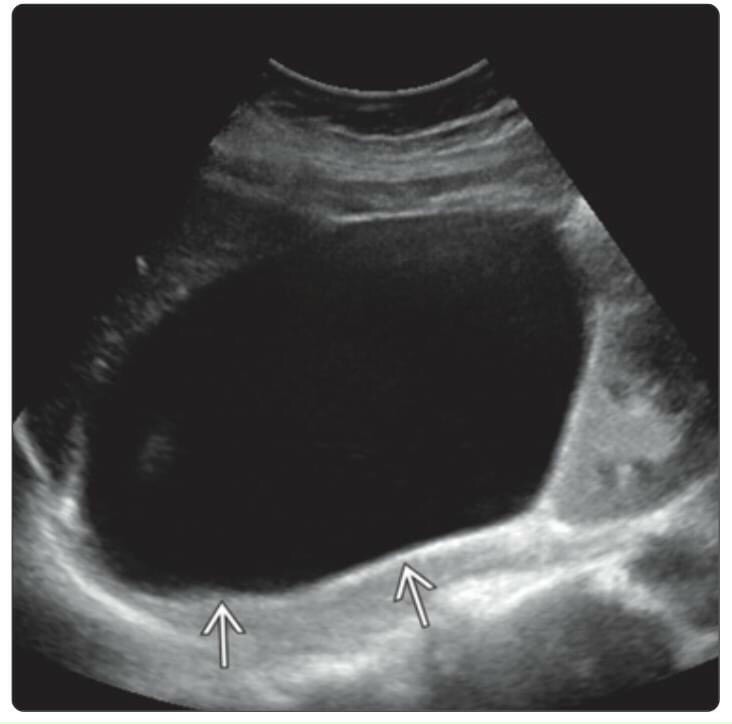

Hình ảnh nang tuyến thượng thận

Hình ảnh nang tuyến thượng thận

Hình ảnh nang tuyến thượng thận

Hình ảnh nang tuyến thượng thận